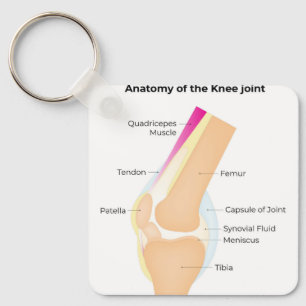

Chaveiro Anatomia do joelho

PreçoR$ 76,65